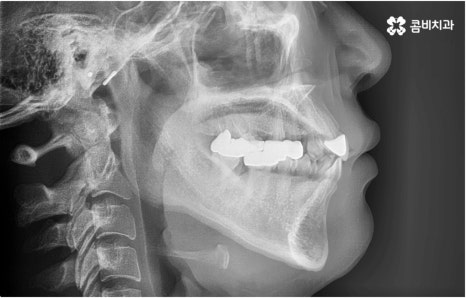

관리의 측면에서 교합이 맞지 않고 치열이 똑바르지 않으면 음식물 찌꺼기가 잘 끼고 잇몸이 붓기 쉽기 때문에 교정 치료가 필요할 수도 있습니다. 씹기가 어렵고 안면비대칭이나 턱관절 통증을 유발하는 등 심각한 부정교합의 경우 기능적으로도 필요하지만 약간 삐뚤어지거나 치아 사이가 벌어진 경우 심미적으로도 한 번쯤 교정 치료를 생각해 보셨을 텐데요, 가격이나 기간, 나이 등 여러 가지 부분이 신경쓰여서 막상 시작하기에 부감을 느끼고 계셨다면 먼저 명동치과 에 내원하셔서 자신에게 필요한 교정 치료가 어떤 것인지 알아보시면 좋을 거예요. 골격적인 원인이 크지 않고 정도가 심하지 않다면 환자분들의 상황에 따라 부분 교정으로 보다 짧고 간편하게 진행하는 경우도 있으니 3D CT 와 같이 정밀 검진 기계를 갖춘 치과에서 숙련된 의료진에게 검진 및 상담부터 받아보시길 권유드리고 있습니다.